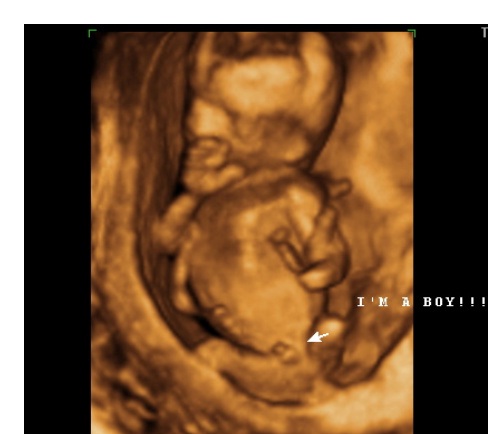

Специалисты обращают внимание на то, что на 18-й неделе можно уже различить пол ребенка с помощью ультразвукового исследования. Это время, когда будущие родители начинают ощущать первые шевеления плода, что становится важным эмоциональным моментом для них. Врачи рекомендуют следить за своим состоянием, правильно питаться и избегать стрессов, чтобы обеспечить оптимальные условия для дальнейшего развития малыша.

| Пол: На УЗИ уже можно определить пол ребенка с высокой точностью. | Могут появиться растяжки на животе, бедрах и груди. | |

На 18-й неделе беременности: вместе с формированием отпечатков пальцев, половые органы вашего малыша почти полностью развиты. Если у вас девочка, то ее фаллопиевы трубы и матка уже на месте. Если это мальчик, вы сможете увидеть его пенис на следующем УЗИ, в зависимости от его положения.